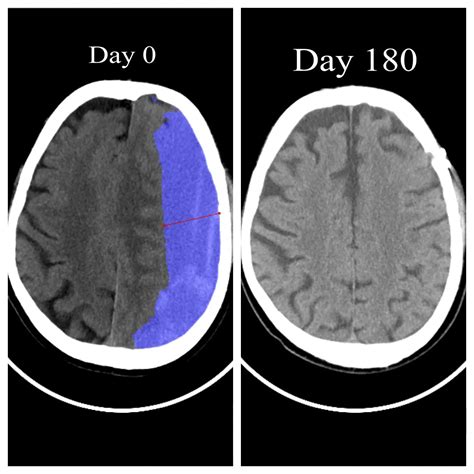

Undergoing a surgical procedure is often a significant milestone on the road to recovery, but the post-operative period comes with its own set of challenges. One of the most common concerns patients encounter during this recovery phase is the development of a hematoma after operation. A hematoma is essentially a localized collection of blood outside of blood vessels, often forming in the space left behind by surgery. While many are minor and resolve on their own, understanding the signs, symptoms, and management strategies is crucial for ensuring a safe and successful healing process.

When a surgeon makes an incision, small blood vessels within the tissue are inevitably disrupted. While surgeons take meticulous care to achieve hemostasis—the process of stopping bleeding—during the procedure, blood can occasionally accumulate in the underlying tissues. This collection is what medical professionals refer to as a hematoma after operation. Factors that increase the risk include the use of anticoagulant medications, underlying clotting disorders, and the sheer complexity or invasiveness of the surgical site.

The appearance of a hematoma can vary significantly based on how deep the collection is and how much blood has gathered. You might notice swelling, discoloration that mimics a bruise, or even a firm, tender lump beneath the surgical site. It is important to distinguish between normal post-operative bruising, which is expected, and a problematic hematoma that may require medical intervention.

The management of a hematoma after operation depends heavily on its size and the symptoms it causes. For very small collections of blood, the body is usually capable of reabsorbing the blood over several weeks. In these cases, your surgeon may simply recommend conservative measures to manage comfort and monitor progress.